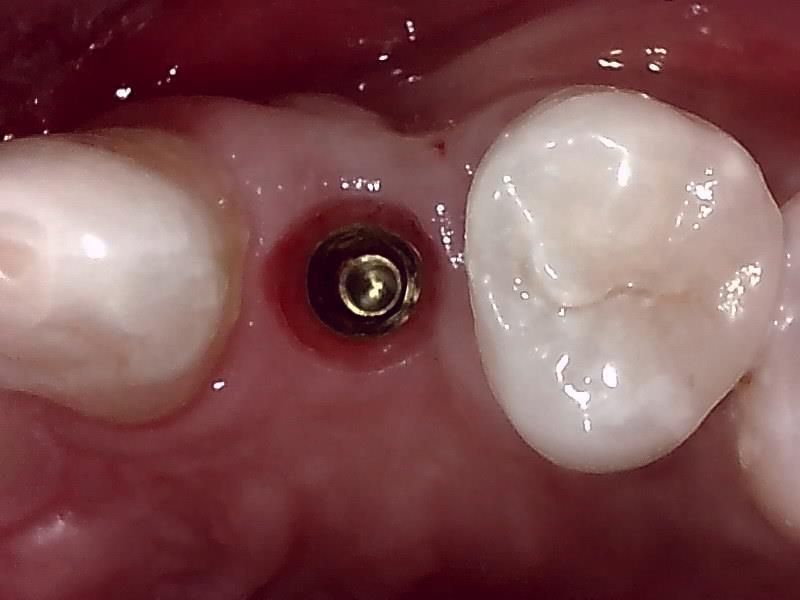

術前の顎堤

顎堤部 歯槽骨にドリリングする。

インプラント体の口径に合わせて埋入孔を形成した状態です。

インプラント埋入した状態は良好です。

術前の時は瘦せていた顎堤が適切なグラフト手技により

しっかりした厚みのある顎堤が隆起している。

インプラント埋入後、10ヶ月経過した健全な顎堤の状態です。